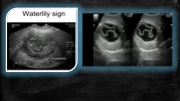

Page 37 - SONO 260 Patologías Hígado - PC2